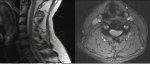

ddd.mri.3.jpg

Началось жжение, щекотание и покалывание в стопах. Спроблемы с равновесием, неуклюжесть. Онемение и слабость в ногах(началось с левой). Похожие но слабые симптомы в руках. Может ли хуйня на моём МРТвызвать эти симптомы?